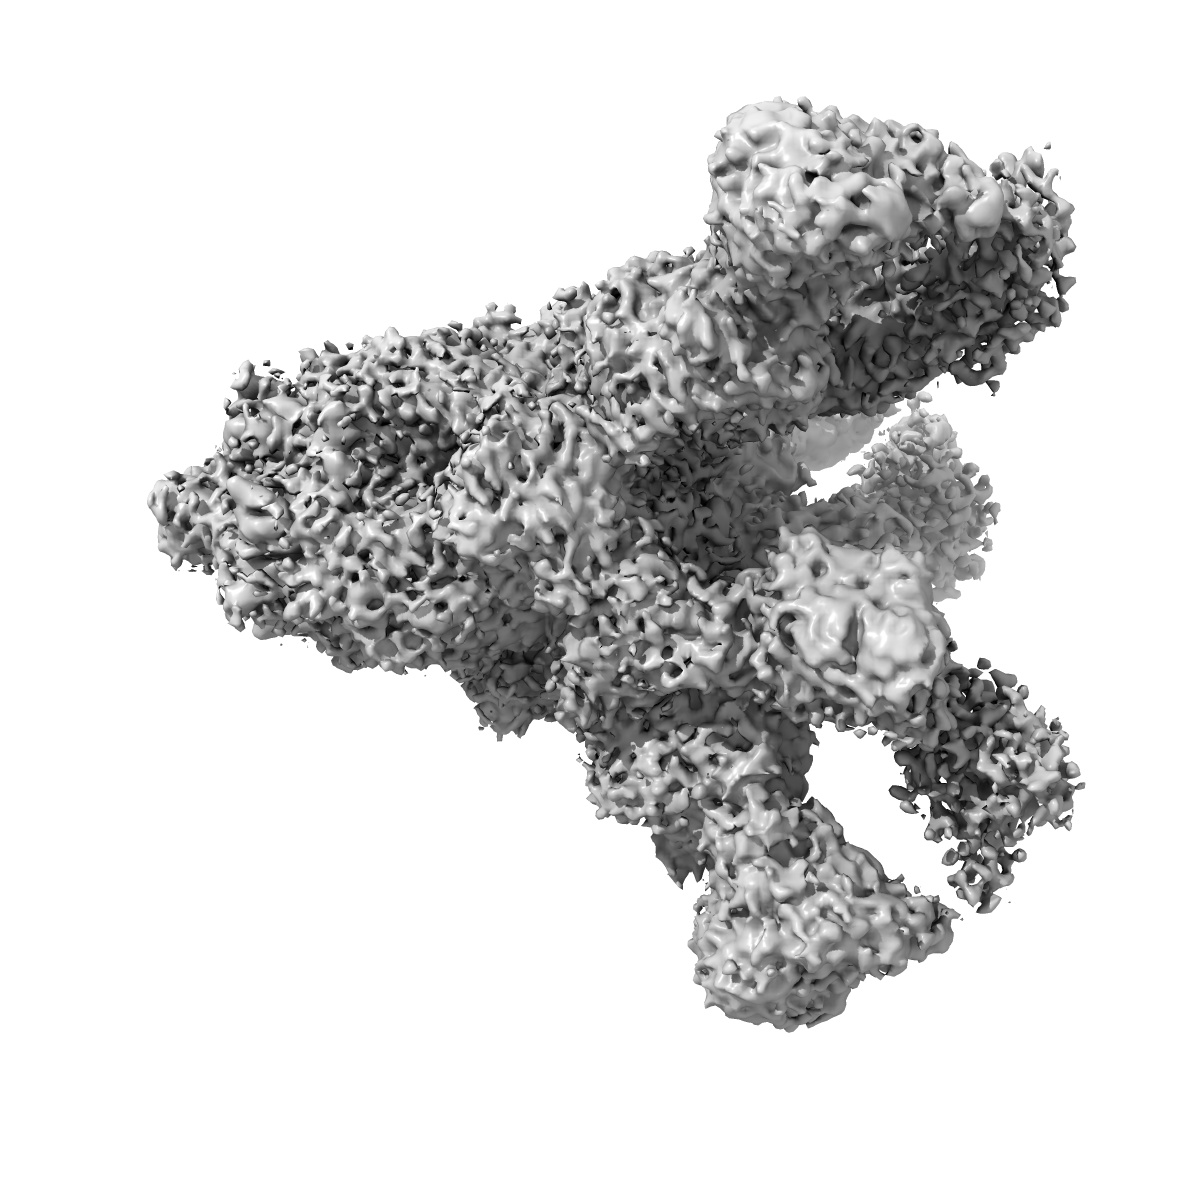

SARS-CoV-2 spike proteins trimer in complex with P17 and FC05 Fabs cocktail

EMD-30488

Single-particle

3.5 Å

Sample: SARS-CoV-2 spike proteins trimer in complex with P17 and FC05 Fabs cocktail

Fitted models: 7cwu

Structure-based development of human antibody cocktails against SARS-CoV-2.

Wang N, Sun Y , Feng R, Wang Y, Guo Y, Zhang L, Deng YQ, Wang L, Cui Z, Cao L , Zhang YJ, Li W, Zhu FC, Qin CF , Wang X

(2021) Cell Res , 31 , 101 - 103